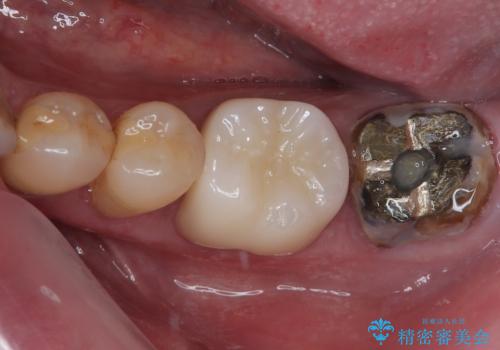

下顎大臼歯の再根管治療とオールセラミッククラウンによる補綴治療

奥歯がうずく